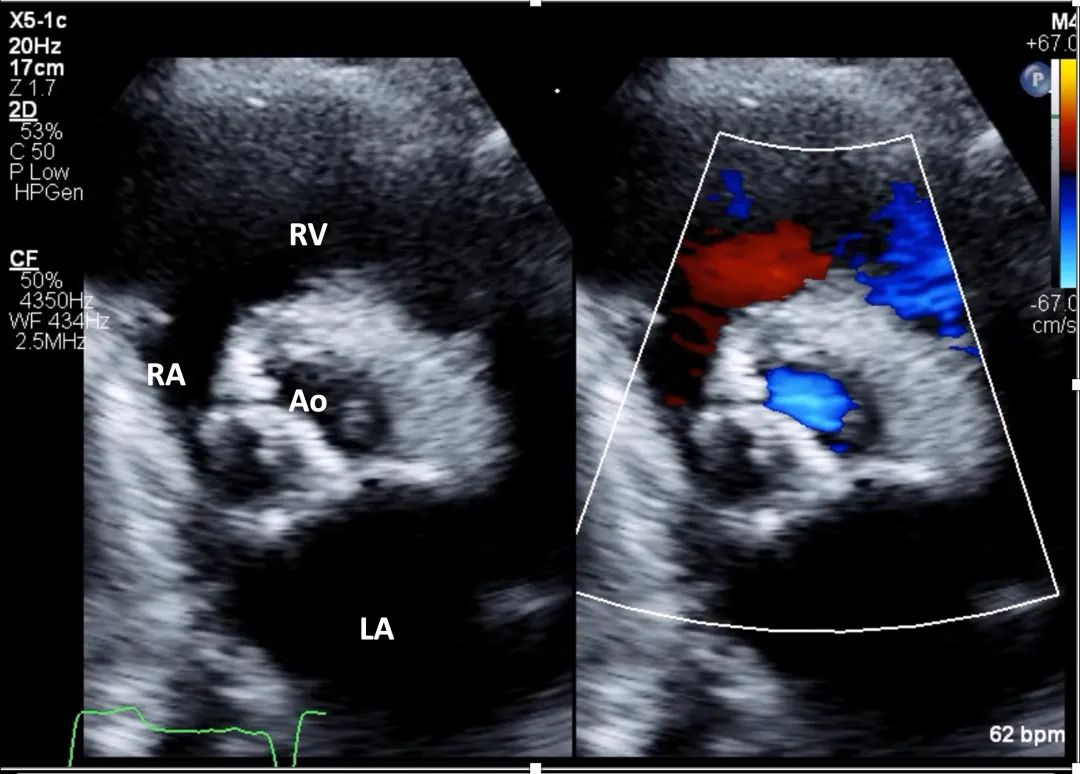

7、心尖五腔心切面: 在主动脉瓣处的彩色多普勒显示主动脉瓣狭窄引起的彩色镶嵌血流(mosaic color flow)模式,且可显示主动脉瓣反流(aortic regurgitation,AR)。应确认湍流起始位置,确保湍流源自瓣膜层面,而非瓣下(如主动脉瓣下隔膜或肥厚型心肌病所致左室流出道梗阻)或瓣上位置(图8,视频5)。

图8. 心尖五腔心切面评价主动脉瓣狭窄(有和彩色多普勒对比)

心尖五腔心切面结合主动脉瓣处彩色多普勒,用于评估流出道梗阻所致狭窄性彩色镶嵌血流模式以及主动脉瓣反流。缩写同图2。